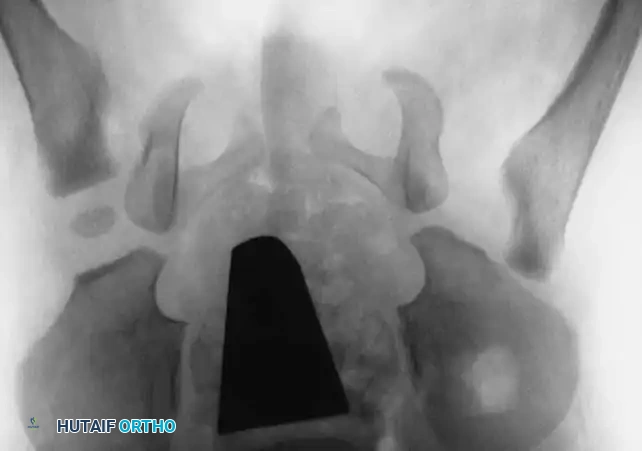

Radiography: Becomes reliable after 4 to 6 months as the ossific nucleus of the femoral head appears. Key radiographic parameters include:

* Hilgenreiner's Line: A horizontal line through the triradiate cartilages.

* Perkins' Line: A vertical line dropped from the lateral margin of the acetabulum, perpendicular to Hilgenreiner's line.

* Shenton's Line: A continuous arc drawn from the medial border of the femoral neck to the superior border of the obturator foramen. Disruption indicates proximal migration.

* Acetabular Index: The angle between Hilgenreiner's line and a line drawn from the triradiate cartilage to the lateral edge of the acetabulum. Normal is <30 degrees in newborns; >35 degrees is highly suspicious for dysplasia.

Radiographic evaluation: Normal hip anatomy (left) versus Dysplastic hip anatomy (right) demonstrating disruption of Shenton's line and an increased acetabular index.